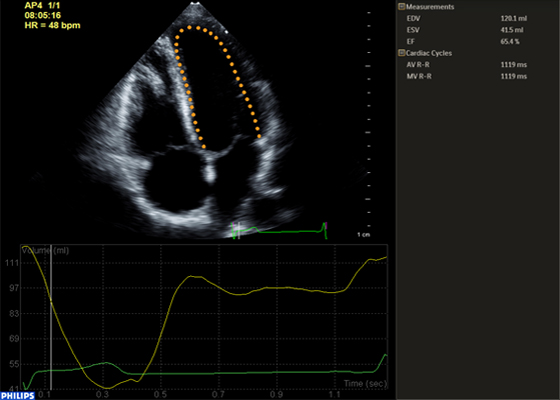

Découvrez HeartModelᴬ⋅ᴵ⋅, une nouvelle application d’intelligence anatomique appliquée à l’échographie (AIUS) intégrant les fonctionnalités suivantes pour l’échocardiographie : quantification 3D temps réel, affichages 2D automatisés et reproductibilité performante. HeartModelᴬ⋅ᴵ⋅ détecte, segmente et quantifie automatiquement l’oreillette gauche et le ventricule gauche à partir d’un volume 3D.

Cette étude a comparé la quantification entre la 2D et HeartModelᴬ⋅ᴵ⋅ 3D temps réel : HeartModelᴬ⋅ᴵ⋅ offre un gain de temps de 82 % lors de l’utilisation de la fonctionnalité d’automatisation et de 63 % lorsque des modifications mineures sont nécessaires.